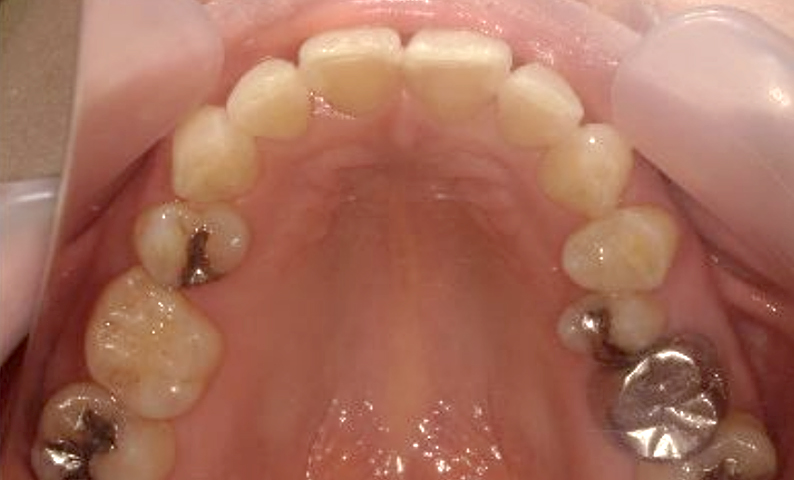

症例_003 下顎だけの部分矯正

治療期間:10ヶ月金額:24万円+税女性前歯のガタガタ下の前歯だけ上顎は補綴治療中

| Before | After |